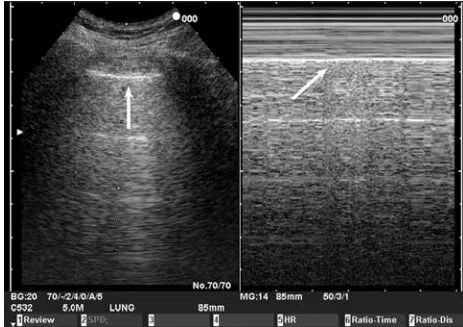

M型模式下的胸壁和胸膜滑动如下图所示,胸壁相对不动,呈横纹表现,肺滑动引起沙粒样改变,称为海岸征或沙滩征。近场显示胸壁层的静态表现(海),远场显示动态胸膜滑动的运动征象(海岸)。

图片

注:左图为B型超声,右图为M型超声